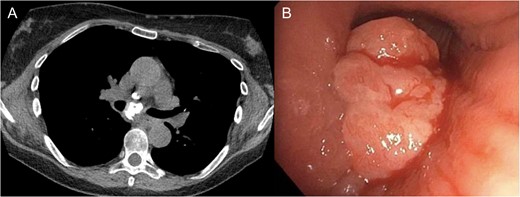

One-year after her original presentation, the patient presented to the emergency room with worsening cough and choking with oral intake. A CT scan of chest revealed a fistula between the right mainstem bronchus and esophagus (Fig. 2A). The patient underwent rigid bronchoscopy revealing a 2-cm defect on the medial wall of the right mainstem bronchus, ~1-cm from the main carina (Fig. 2B). A CT esophagram confirmed extravasation of oral contrast into the tracheobronchial tree (Fig. 3).

(A) CT scan revealing fistula between the right mainstem bronchus and esophagus. (B) Endobronchial view visualizing right mainstem defect.